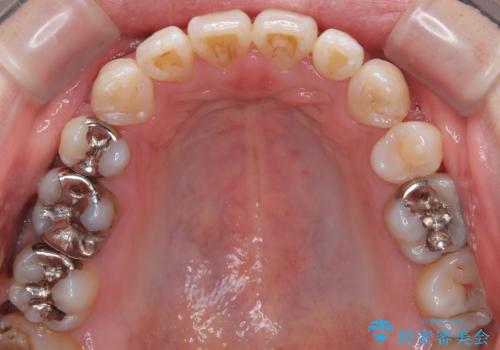

精密検査の結果、上下左右の小臼歯4本を抜歯し、そのスペースに前歯を後方へ移動させる矯正治療をご提案しました。

装置は、透明感のあるクリアブラケットとホワイトコーティングされたワイヤーを使用した、目立ちにくい審美装置を選択。